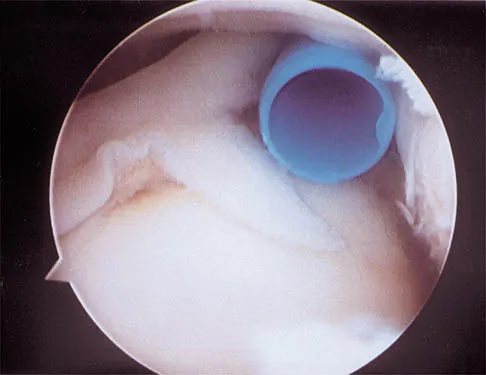

Which of the following anatomic structures is often difficult to visualize during elbow arthroscopy?

Explanation

The ulnar collateral ligament is often difficult to visualize during elbow arthroscopy. It can be seen clearly in only 10% to 30% of elbow arthroscopies. All of the other structures should be easily and thoroughly seen and palpated during elbow arthroscopy. Johnson LL: Arthroscopic Surgery: Principles and Practice. St Louis, MO, CV Mosby, 1988.